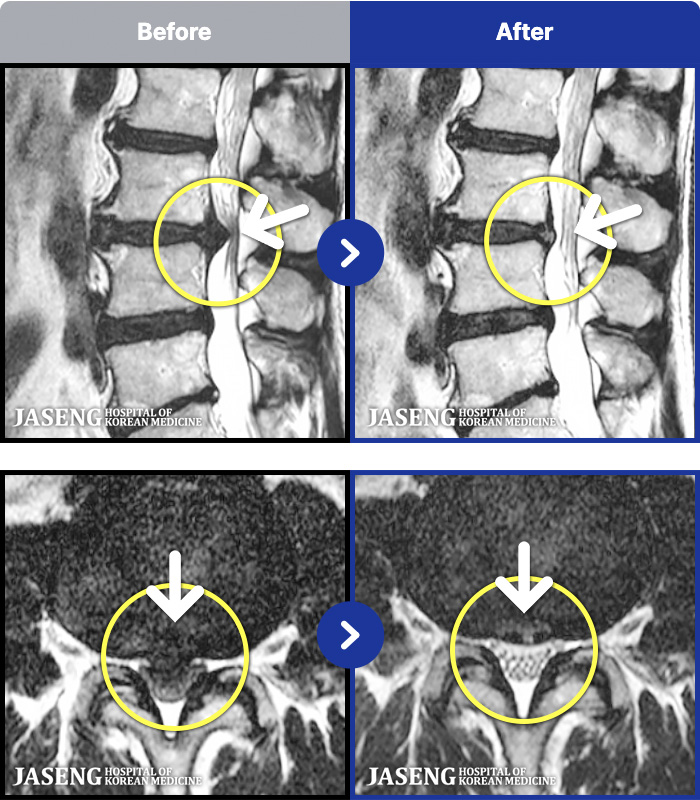

MRI ġ

1,245 MRI ũ ʸ Ȯϼ.